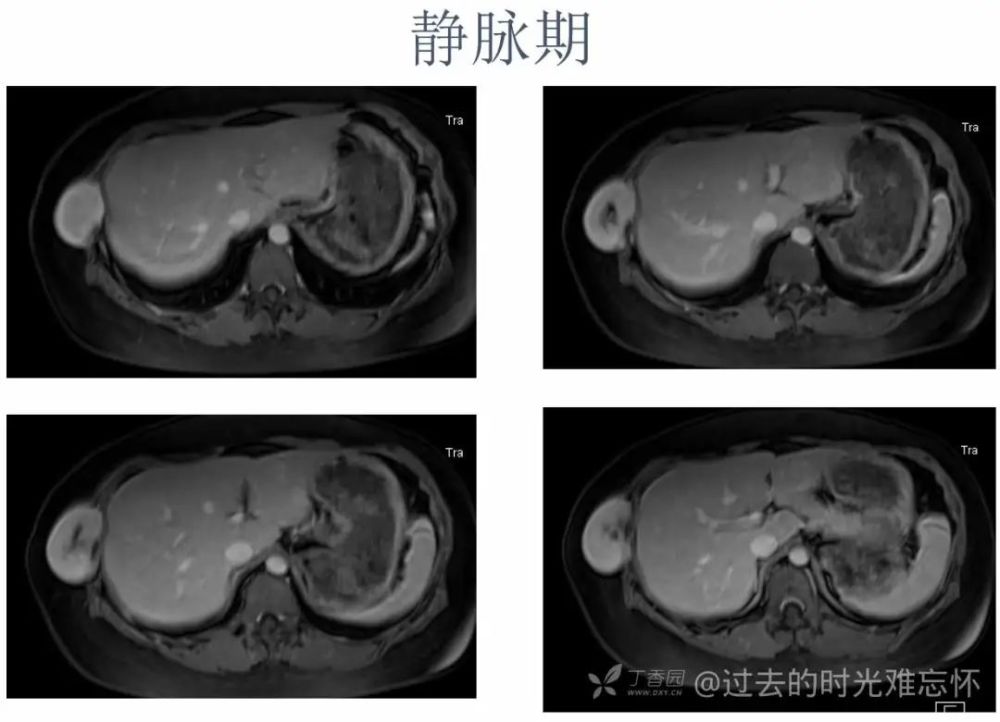

女,22 岁。右下侧胸壁疼痛、不适 10 年,近 3 年发现右侧腋中线近肋弓处肿块。体检:局部皮肤无红肿,肿块质中等偏硬,活动度欠佳,压痛( + ),无血管杂音。超声描述「低回声包块」。化验室指标无异常。